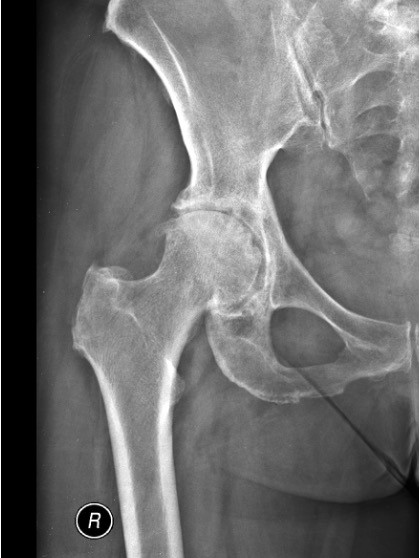

ΠΟΙΑ ΕΙΝΑΙ Η ΣΥΧΝΟΤΕΡΗ ΠΑΘΗΣΗ ΠΟΥ ΠΡΟΣΒΑΛΕΙ ΤΗΝ ΑΡΘΡΩΣΗ ΤΟΥ ΙΣΧΙΟΥ?

Η οστεοαρθρίτιδα είναι ο πιο συχνός τύπος αρθρίτιδας ο οποίος εκτός από το ισχίο μπορεί να προσβάλει σχεδόν όλες τις αρθρώσεις.

Συμβαίνει όταν για διάφορους λόγους ο χόνδρος που βρίσκεται στην επιφάνεια των αρθρώσεων εκφυλίζεται και στα τελικά στάδια καταστρέφεται.

Τα συχνότερα συμπτώματα αυτής της εκφύλισης είναι ο πόνος και η δυσκαμψία της άρθρωσης.

Στα τελικά στάδια η οστεοαθρίτιδα γίνεται πολύ επώδυνη, δεν αντιμετωπίζεται συντηρητικά με παυσίπονα και αντιφλεγμονώδη φάρμακα και επηρεάζει αρνητικά την ποιότητα ζωής του πάσχοντος.

Τότε η μόνη λύση είναι να γίνει αντικατάσταση της προσβεβλημένης άρθρωσης με ειδικές προθέσεις / αρθροπλαστικές.

Η διάγνωση της οστεοαρθρίτιδας γίνεται αξιολογώντας τα συμπτώματα και συνήθως με μία απλή ακτινογραφία της άρθρωσης.